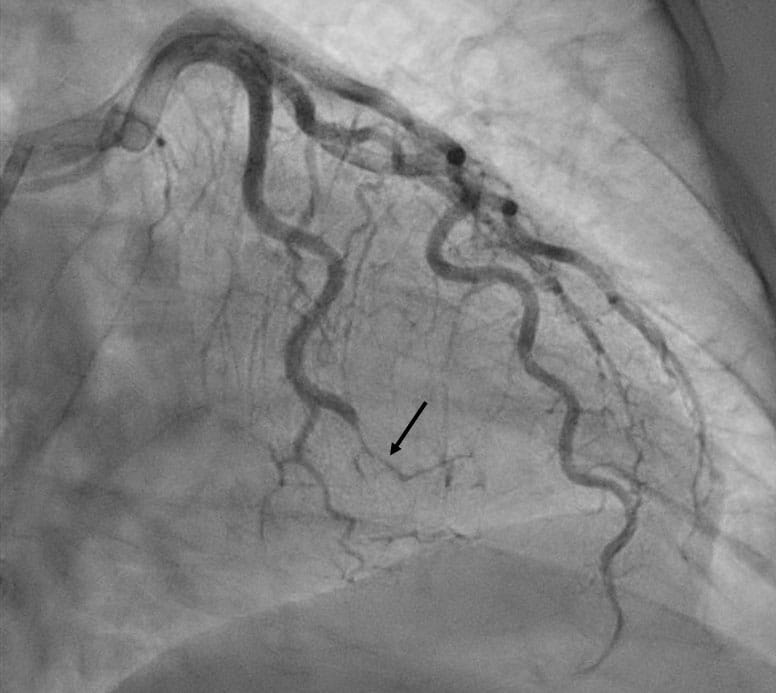

Spontaneous coronary artery dissection (SCAD) of an obtuse marginal artery (arrow) in a 62-year-old woman with non ST-segment elevation myocardial infarction. She was managed with medical therapy.  She was subsequently found to have FMD in multiple arteries and evidence of a prior silent vertebral artery dissection. Note is made of tortuosity of the coronary arteries, a finding that has been associated with SCAD.Caption: Spontaneous coronary artery dissection (SCAD) of an obtuse marginal artery (arrow) in a 62-year-old woman with non ST-segment elevation myocardial infarction. She was managed with medical therapy. She was subsequently found to have FMD in multiple arteries and evidence of a prior silent vertebral artery dissection. Note is made of tortuosity of the coronary arteries, a finding that has been associated with SCAD.

Heart attack blockages resulting from SCAD differ significantly from more common forms of heart attack. “Interventional cardiologists play a crucial role in determining that a coronary dissection is occurring,” says Dr. Gornik. “These patients tend to have a high risk of complication with coronary angioplasty and stenting, and the blockages due to SCAD are often best managed with medications. But the first step is recognizing on the coronary angiogram that the coronary artery narrowing is due to SCAD and not a typical stenosis. I feel fortunate that, at University Hospitals, we have the experts available to recognize SCAD and offer the differentiated care SCAD requires.”